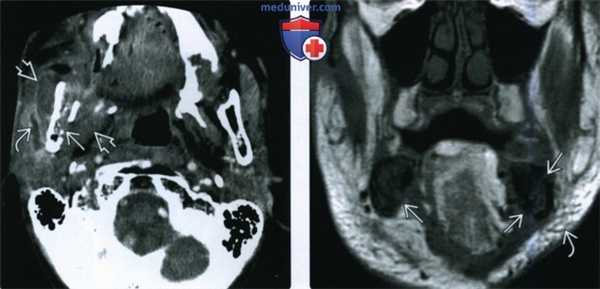

(Слева) При аксиальной КТ с КУ определяется остеорадионекроз нижней челюсти справа, осложненный инфицированием жевательного пространства. Определяется также нарушение целостности кортикальной пластинки и диффузный, выраженный отек жевательных мышц и околоушной слюнной железы, расширение ее выводного протока, заполненного дебрисом воспалительного характера.

(Справа) При МРТ Т1ВИ в корональной проекции определяется диффузное замещение сигнала, в норме наблюдающегося в костном мозге, и характерного для жира. Пристствуют множественные участки нарушения целостности кортикальной пластинки. Индурация и отек подкожных тканей являются часто встречающимися изменениями при остерадионекрозе нижней челюсти.